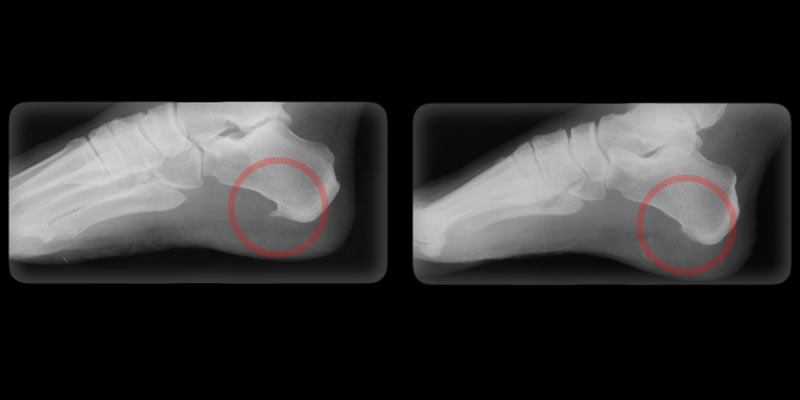

BEFORE      AFTER

Heel Pain

Heel pain is usually caused by acute or chronic inflammation of the plantar fascia, a ligament-like structure located on the bottom of the foot. Inflammation of the plantar fascia can be caused by heel spur or by gout, arthritis, obesity, and other local and systemic diseases.